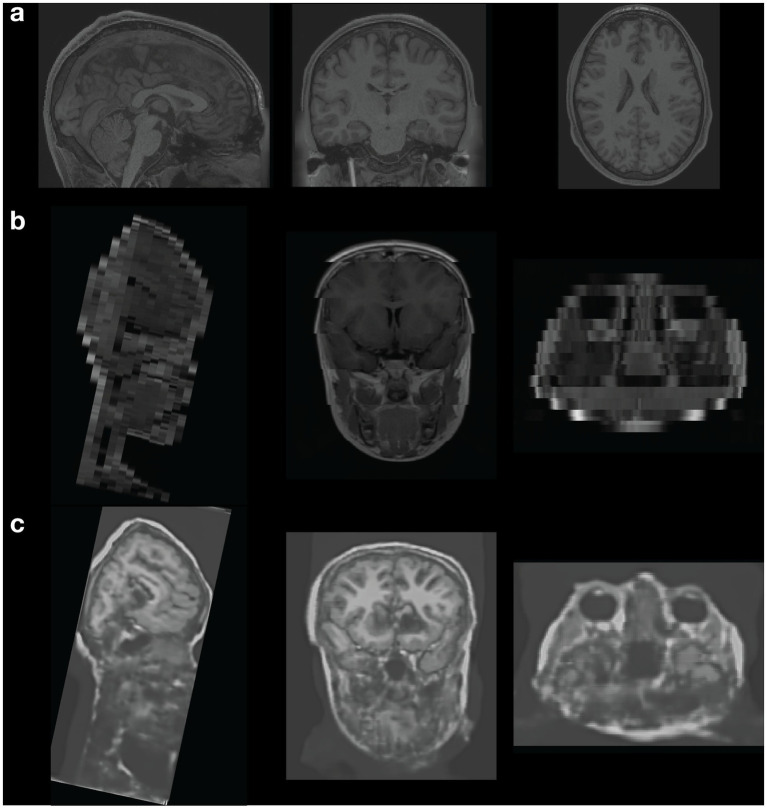

Abstract Image